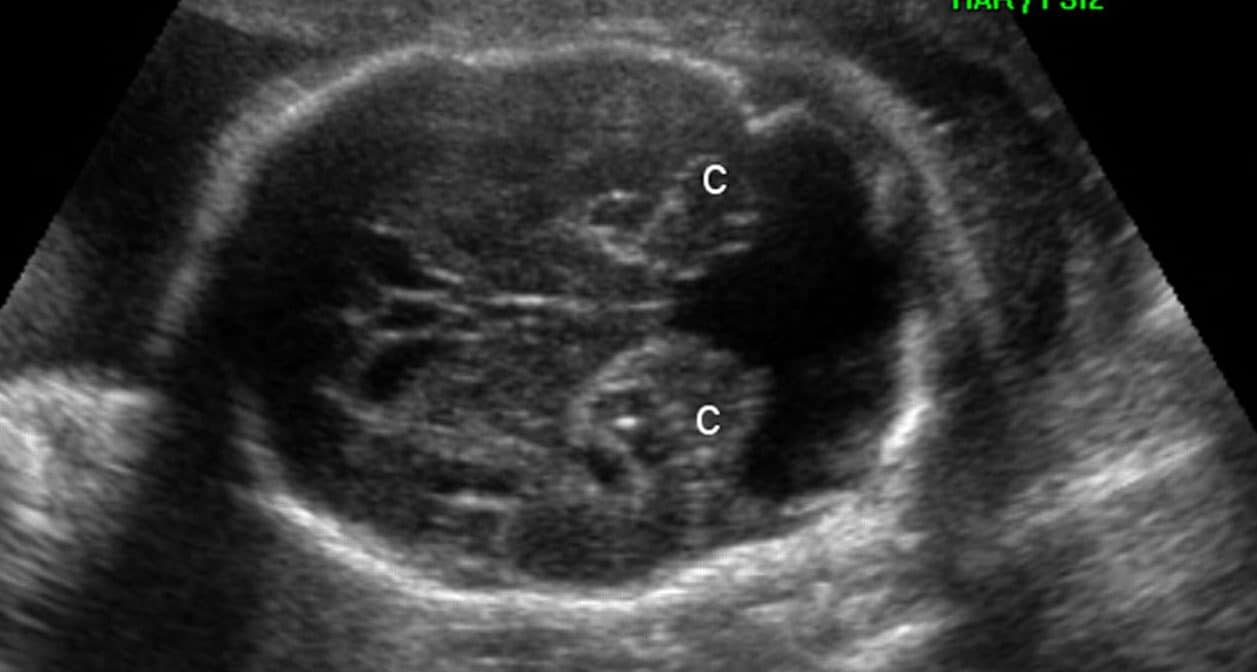

A malformação adenomatóide cística de pulmão (MAC) resulta do desenvolvimento anômalo dos bronquíolos terminais e respiratórios, com proliferação adenomatóide e formação de cistos. Atualmente, a…

A malformação de Dandy-Walker é uma malformação cerebral caracterizada por hipoplasia ou agenesia do vérmis cerebelar e dilatação do quarto ventrículo, com formação cística na…